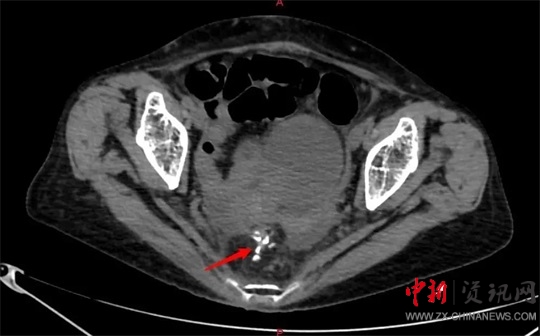

劉大勇對(duì)侯老太太進(jìn)行仔細(xì)的體格檢查及相關(guān)的影像學(xué)檢查后,考慮患者已經(jīng)急性直腸穿孔,且出現(xiàn)了血壓下降、心率增快、脈搏細(xì)弱等休克癥狀,就迅速把侯老太太的病情匯報(bào)給了胃腸外科、疝與腹壁外科主任廖新偉。當(dāng)晚8點(diǎn)左右,廖新偉立即組織科室進(jìn)行會(huì)診。大家一致認(rèn)為患者病情危重,隨時(shí)可能出現(xiàn)生命危險(xiǎn),急診手術(shù)刻不容緩。

當(dāng)晚9點(diǎn)40分,廖新偉積極協(xié)調(diào),麻醉科手術(shù)部及輸血科密切配合,以劉大勇主刀、副主任醫(yī)師汪麗偉輔助,緊急為侯老太太施行了手術(shù)。打開(kāi)腹腔,驚人地發(fā)現(xiàn)侯老太太腹腔已被糞便填滿,腸子漲的像氣球那么大。術(shù)中,經(jīng)過(guò)沖洗并且減壓腸道后,醫(yī)護(hù)團(tuán)隊(duì)在直腸上段發(fā)現(xiàn)一大小約1.5cm破口,一堅(jiān)硬物嵌頓在破口處,打開(kāi)腸壁,一排帶鉤的假牙映入眼前。醫(yī)護(hù)人員將假牙小心翼翼地完整取出,足足有4cm長(zhǎng)。由于侯老太太腹腔污染嚴(yán)重,且腸梗阻時(shí)間較長(zhǎng),腸壁水腫十分嚴(yán)重,無(wú)法再次重建消化道,于是胃腸外科團(tuán)隊(duì)給老太太做了直腸遠(yuǎn)端封閉+乙狀結(jié)腸造口術(shù)。考慮到患者腹腔污染術(shù)后可能出現(xiàn)感染腹腔膿腫等情況,醫(yī)護(hù)團(tuán)隊(duì)給侯老太太左右上下總共放了5根引流管。